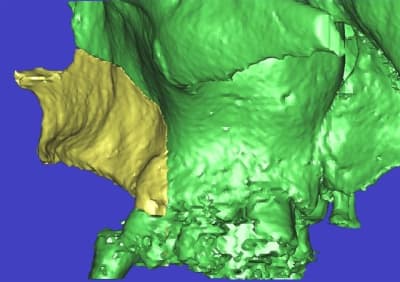

l'étude en partant des blocs standards

La première diapo est un essai pour justifier le concept (os non destiné à une utilisation greffe)

la deuxième est "tapée" dans une tête de femur de mauvais qualité (rejetée)

la troisième et suivante ce sont "les greffons" définitifs.